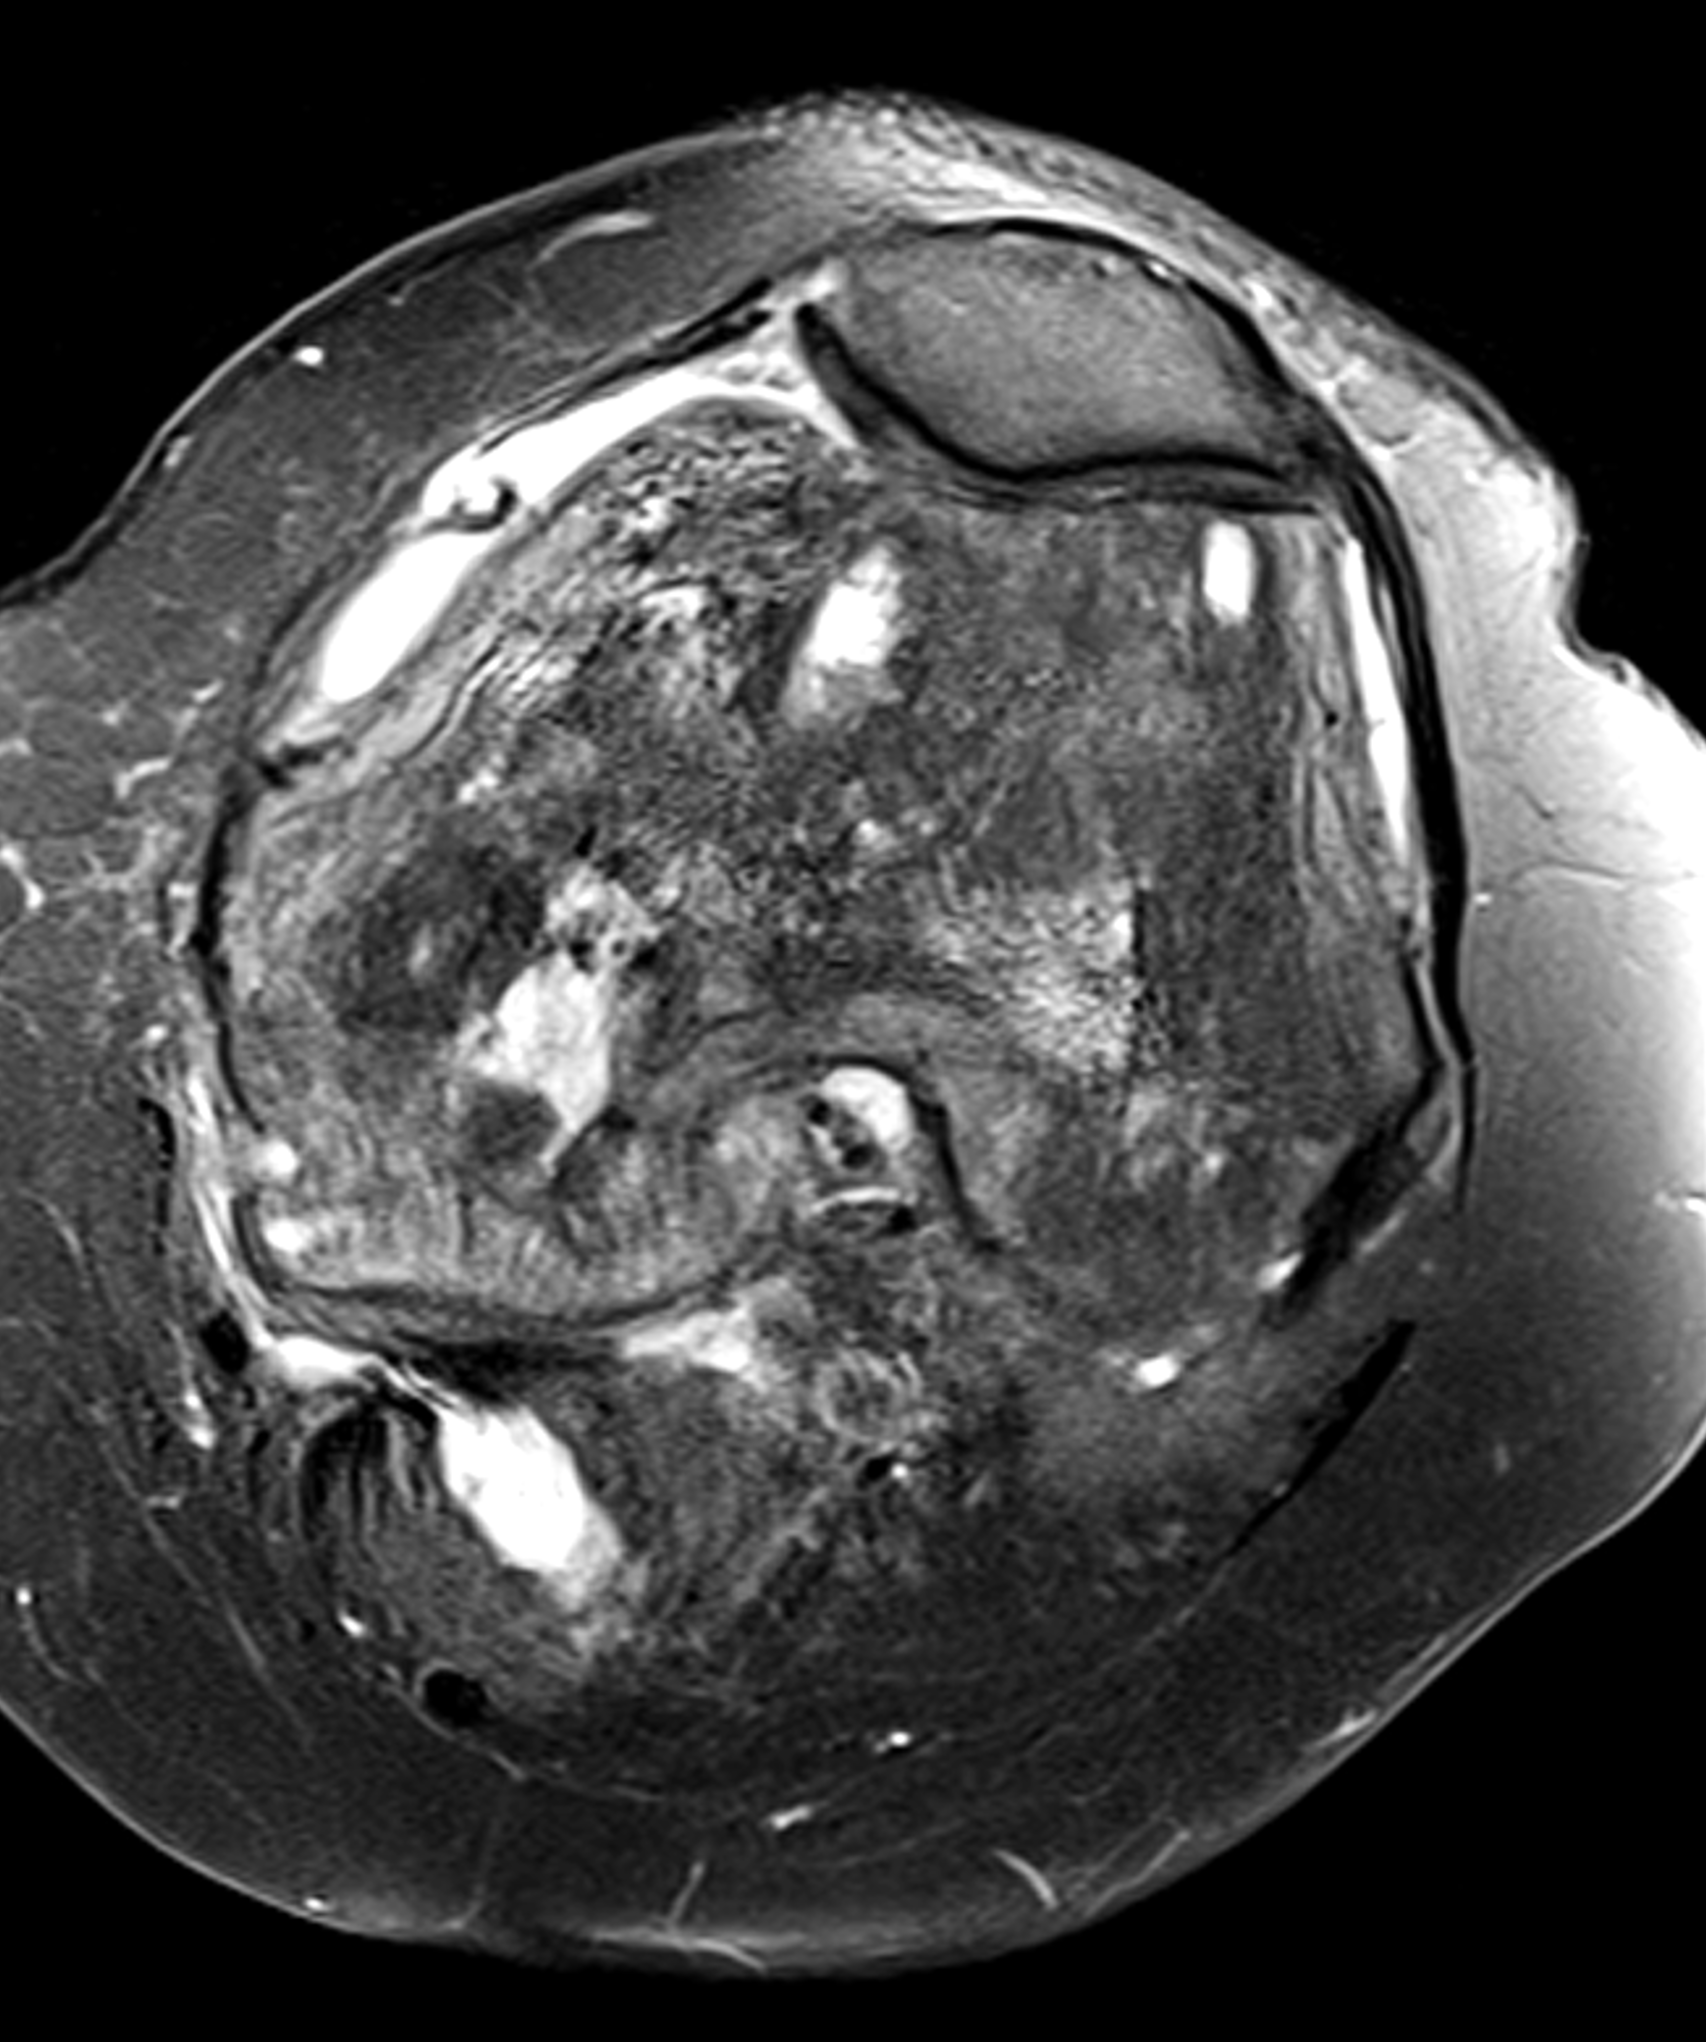

An elderly man presents with generalized knee pain. A sagittal T1-weighted image (1A) of the knee, axial fat-suppressed, fluid sensitive images through the distal femoral shaft (1B) and femoral condyles (1C), and an AP radiograph (1D) of the knee are provided. What are the findings? What is your diagnosis?

Figure 2: (2A) Sagittal T1-weighted image shows severe thickening of the distal femoral cortex (yellow arrow) and thickening and coarsening of the trabeculae in the femoral condyles (red arrow). Note the high signal intensity fatty marrow in both regions. (2B) Axial fat-suppressed, fluid sensitive sequence through the distal femoral shaft shows severe thickening of the bone cortex, with small round and tubular high-signal intensity foci within the cortex (arrow), likely representing cysts and dilated vascular spaces. (2C) Axial fat-suppressed, fluid sensitive sequence through the femoral epicondyles shows heterogeneous marrow (asterisks), with areas of suppressed marrow fat, mildly increased marrow signal intensity, and small cyst-like lesions. (2D) AP radiograph shows typical findings of mixed phase Paget disease in the distal femur including cortical thickening, course trabeculae, and bone enlargement. Secondary medial compartment predominant osteoarthritis has developed, likely contributing to symptoms.